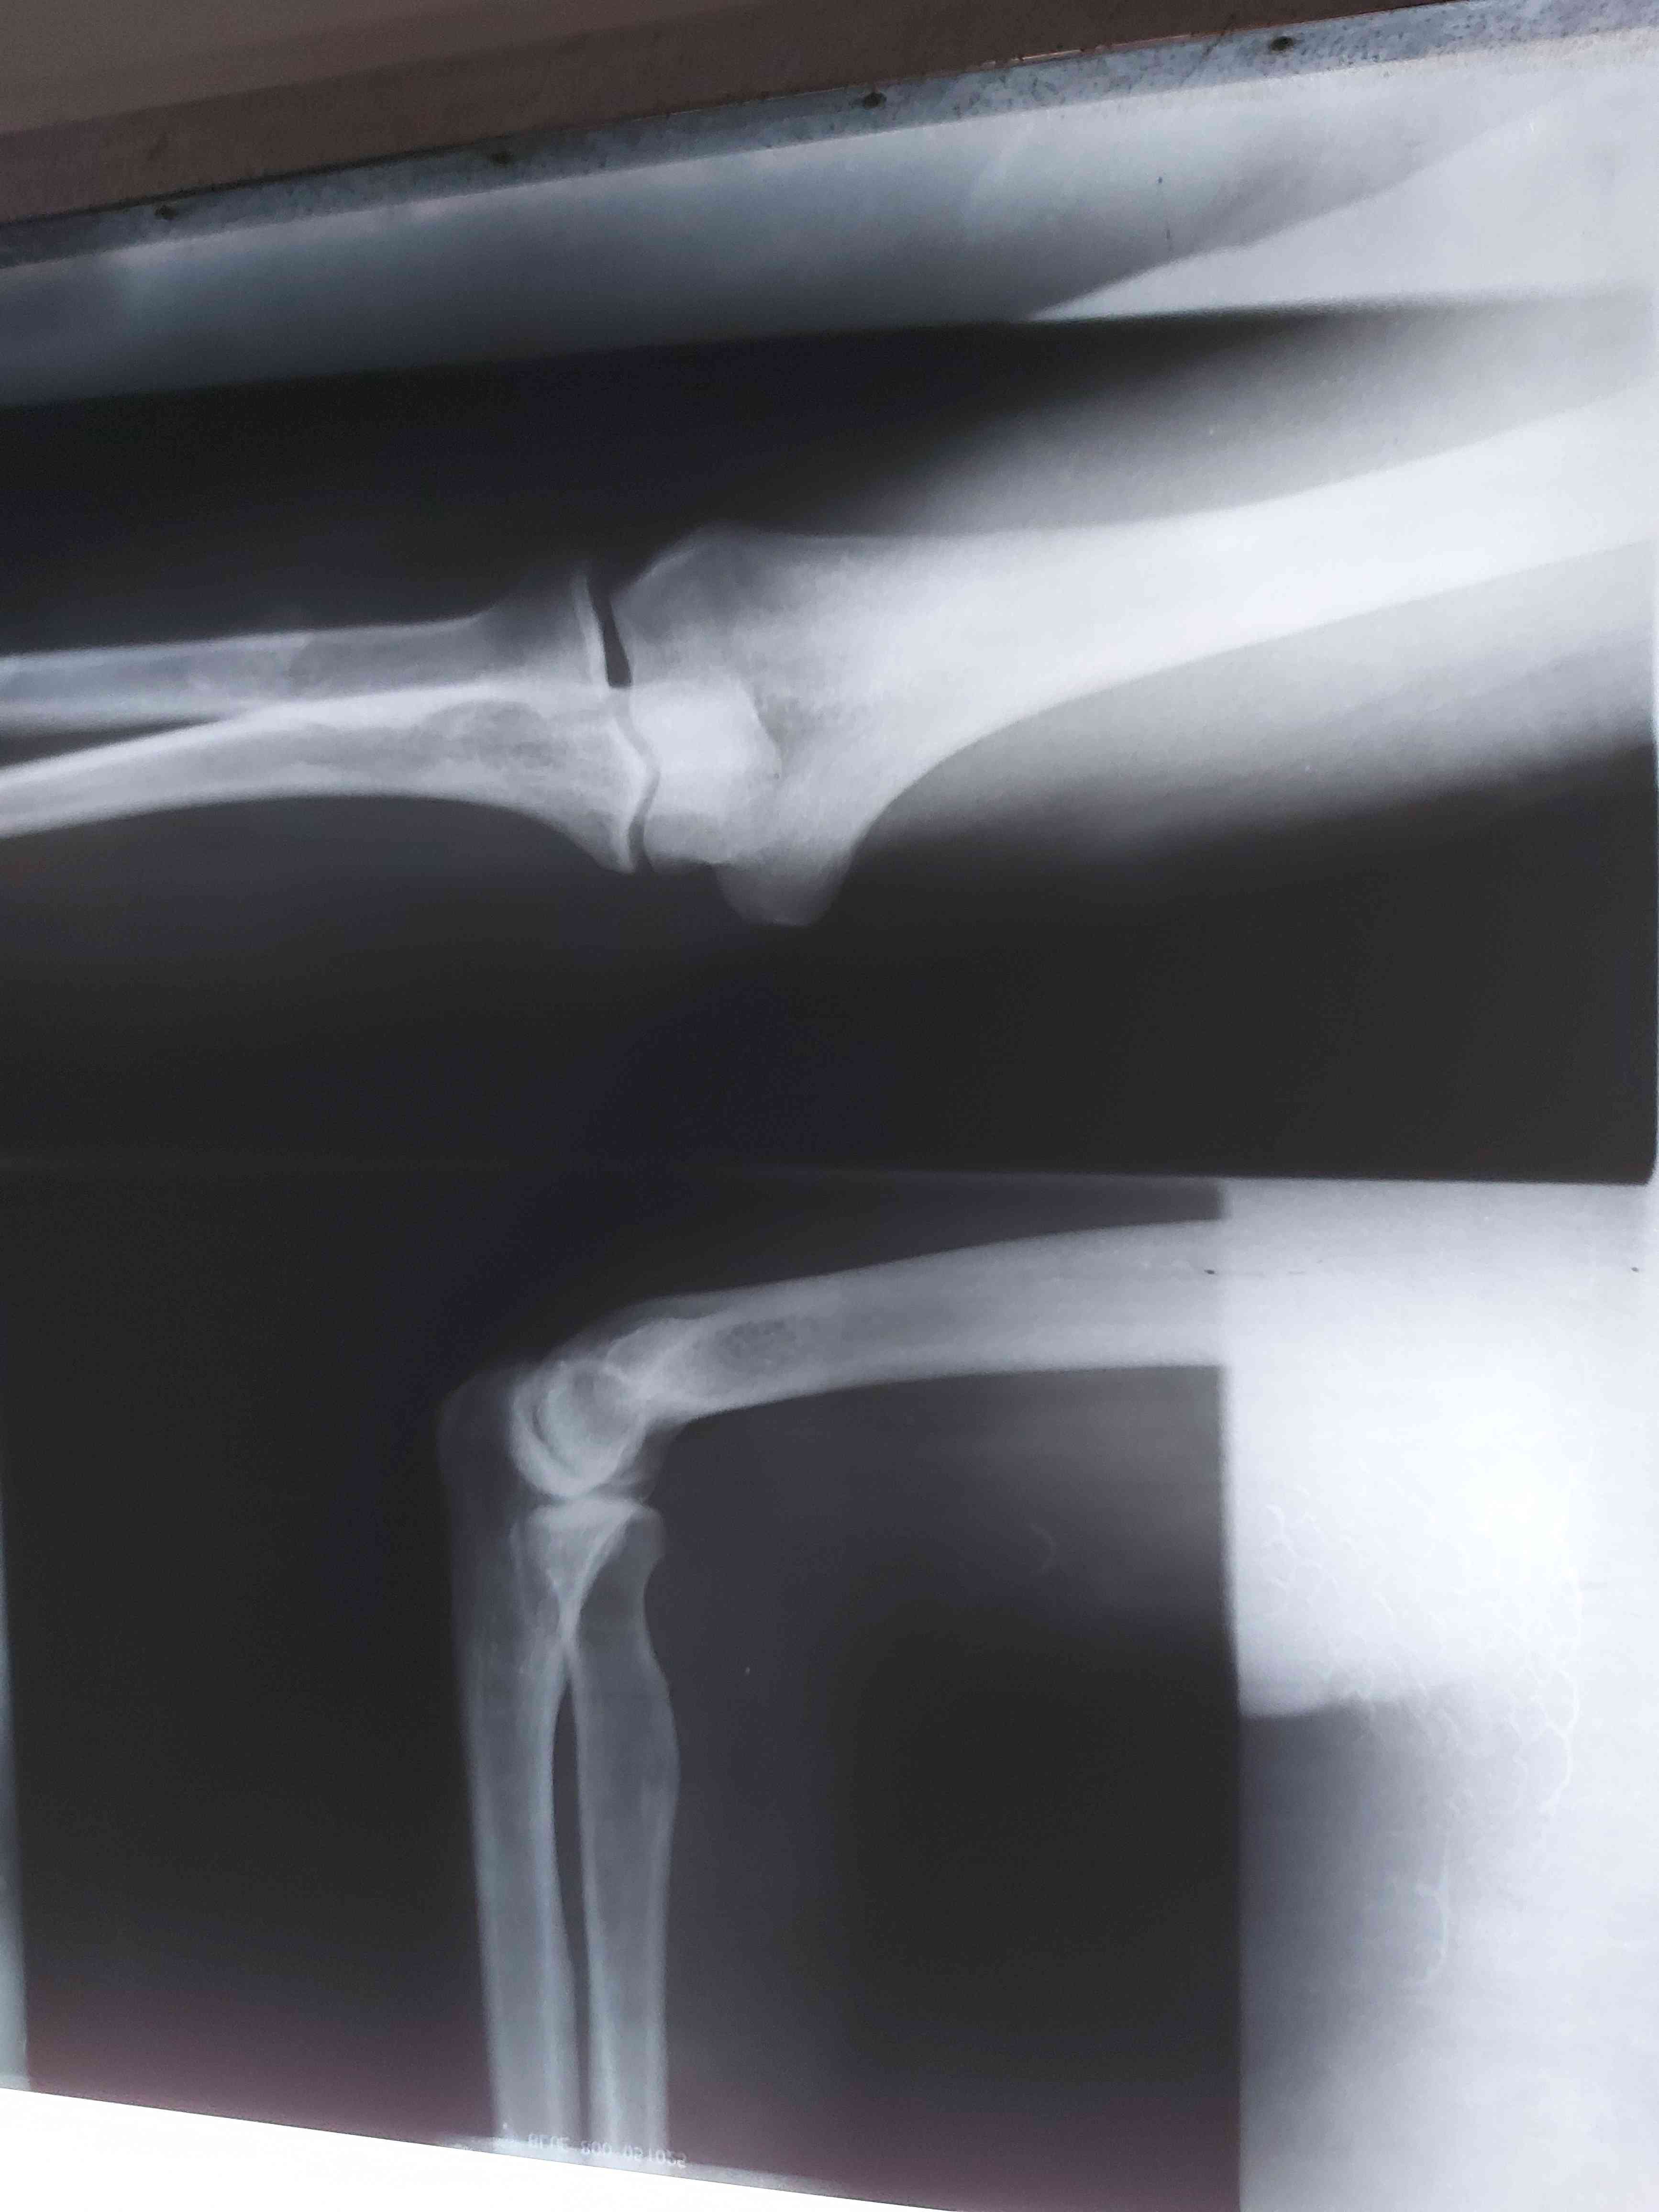

الم في ذراعي وساقي وكل التحاليل سليمه

الم في ذراعي وساقي وكل تحاليلي سليمه

الفحص السريري مهم هل تم فحص الرقبه واسفل الظهر وهناك تحاليل كثيره ومتنوعه كلها تعتمد على الفحص السريري أنصحك بمراجعة طبيب روماتيزم لاجراء اللازم او لتوجيهك للتخصص المعني 0 2021-04-04T19:24:22+00:00